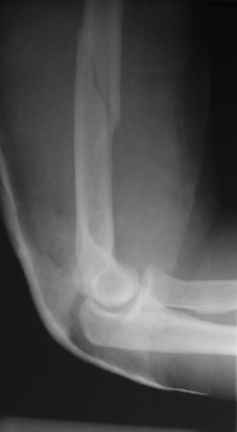

Снимки до, через 1 и 2 мес. после синтеза.

Теперь непосредственно по больному. Лечим функциональной повязкой, добились вот чего (приложение). Будем признательны за дальнейший комментарий - мое мнение, что можно продолжить без операции.